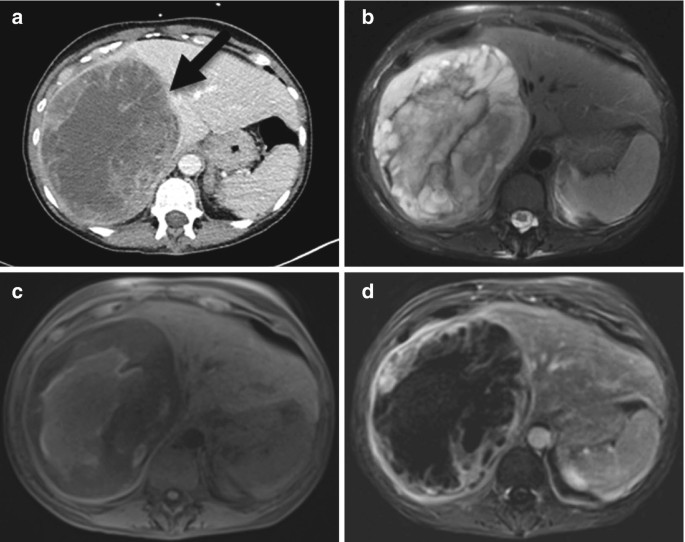

From link.springer.com

Complex Cystic Liver Lesion SpringerLink Differentials For Abdominal Pain Find out the causes, tests, and imaging studies for. Learn how to assess and manage patients with acute abdominal pain, a common presenting concern with a broad differential diagnosis. Learn how to make differential diagnoses based on the regional location of your patient’s abdominal pain. A comprehensive list of causes and differential diagnoses for abdominal pain, organised by region and. Differentials For Abdominal Pain.